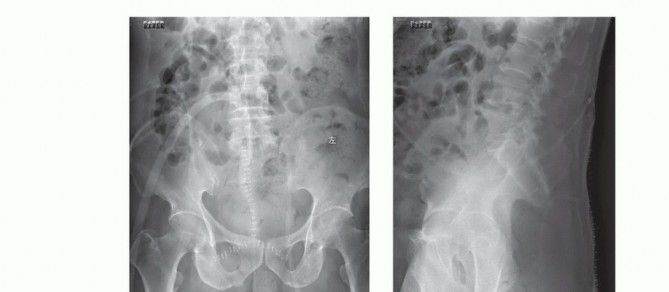

التصوير بالأشعة السينية العادية

قد تكون صور الأشعة السينية العادية غير واضحة في المراحل المبكرة من المرض. ومع ذلك، يمكن أن تساعد في تشخيص بعض الأورام، مثل الورم الحبلي الذي غالبًا ما يقع في الجزء السفلي من العجز، أو الأورام الكبيرة والمحللة تمامًا مثل ورم الخلايا العملاقة أو الكيس العظمي المتمدد في الجزء العلوي من العجز. تُعد الأشعة السينية ضرورية لإعطاء نظرة عامة ومتابعة ما بعد الجراحة.

التصوير المقطعي المحوسب والرنين المغناطيسي

- التصوير المقطعي المحوسب (CT): يُعد بتقنية التباين الوريدي الأسلوب الأمثل لتقييم مدى انتشار الورم في العظم وتدميره، والتكلسات المحتملة، والموقع التشريحي، والإمداد الدموي، وعلاقة الورم بالأعضاء الحشوية. يساعد في التفريق بين الأورام الحميدة والخبيثة.

- التصوير بالرنين المغناطيسي (MRI): بتقنية التباين، يُعد حاسمًا لتصوير الأنسجة الرخوة ومدى انتشار الورم فيها، وعلاقته بالأنسجة المحيطة (مثل الأوعية الدموية والأعصاب والعضلات والأعضاء الحشوية). يُعتبر الأسلوب الأمثل لتصوير الأنسجة الرخوة نظرًا لقدرته الفائقة على التمييز مقارنةً بالتصوير المقطعي.

التخطيط قبل الجراحة

يُعد التخطيط الدقيق قبل الجراحة أمرًا حاسمًا لنجاح العملية. يقوم الأستاذ الدكتور محمد هطيف بمراجعة شاملة لجميع صور ما قبل الجراحة (الأشعة السينية، التصوير المقطعي، الرنين المغناطيسي، تصوير الأوعية الدموية) لتحديد خطة جراحية واضحة وتقييم الدواعي والمخاطر.